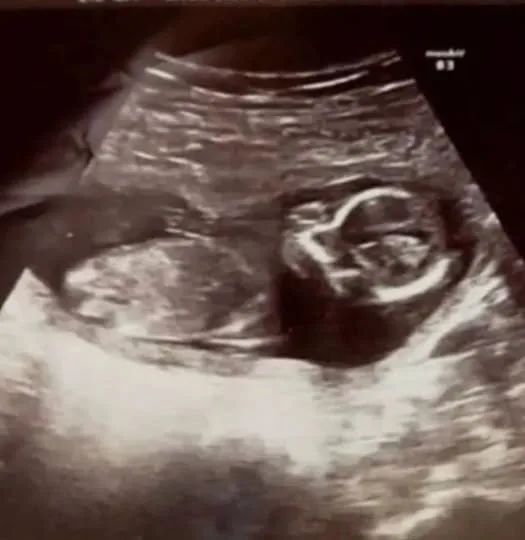

“The doctor left, then came back with a colleague. He did another ultrasound and said, ‘You won’t believe it, but we can hear a heartbeat!'” Michelle says. “That was the happiest moment of my life!” Little Megan was born beautiful and healthy, which surprised the doctors and her parents.

It is unknown whether something like this has happened before. But the most important thing is that now the little one is growing to the joy of her parents, sister Ma and brother Noah. Still, it is amazing how doctors did not notice Megan on previous ultrasounds.